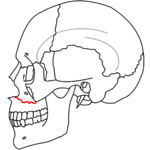

| Le Fort I fractures | |

At the beginning of the 20th century, René Le Fort mapped typical locations for facial fractures; these are now known as Le Fort I, II, and III fractures (right).[6] Le Fort I fractures, also called Guérin or horizontal maxillary fractures,[13] involve the maxilla, separating it from the palate.[14] Le Fort II fractures, also called pyramidal fractures of the maxilla,[15] cross the nasal bones and the orbital rim.[14] Le Fort III fractures, also called craniofacial disjunction and transverse facial fractures,[16] cross the front of the maxilla and involve the lacrimal bone, the lamina papyracea, and the orbital floor, and often involve the ethmoid bone.[14] are the most serious.[17] Le Fort fractures, which account for 10–20% of facial fractures, are often associated with other serious injuries.[14] Le Fort made his classifications based on work with cadaver skulls, and the classification system has been criticized as imprecise and simplistic since most midface fractures involve a combination of Le Fort fractures.[14] Although most facial fractures do not follow the patterns described by Le Fort precisely, the system is still used to categorize injuries.[5]